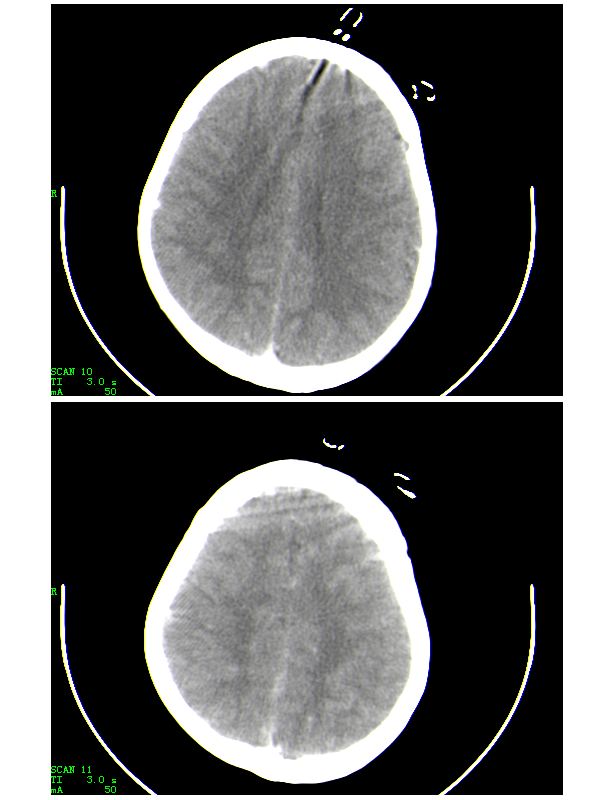

下面是第二天的复查和受伤后第五天的复查,左侧硬膜下血肿有所吸收,脑内条状高密度无改变

第五天的复查片

导致的原因楼上的战友已经讲的非常好了,再加深点印象

人体血液中影响ct值的主要成分是有形成分红细胞和血浆中的蛋白质,尤其室含铁的hb,其占血液中蛋白质总量的大部分,亦是引起血液ct密度变化的主要因素。hb含量与ct值间具有相关性,noman等的研究表明hb含量每改变10g/l,相应ct值变化为1.86hu。

本病主要应与蛛网膜下腔出血相鉴别,鉴别要点:

(1)高密度血管网络旁仍见清晰、正常低密度脑脊液影;

(2)临床没有急性颅内出血的症状何体征。